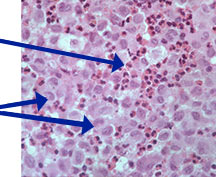

Microscopic Pathology

- Langerhans cell is diagnostic and clonal proliferation

- Nuclei show prominent nuclear groove (coffee-bean)

- Also composed of eosinophils and other inflammatory cells (non diagnostic component)

- Ratio of inflammatory cells to Langerhans cells varies

- Mitotic activity low

- Eosinophils dominate some areas forming diffuse sheets, excluding Langerhans cells

- Birbeck Granules: Electron Microscopy demonstrates granules that often take the form of a tennis raquet and form from complex invaginations of the cell membrane

- Vimentin, CD1 and S-100 positivity